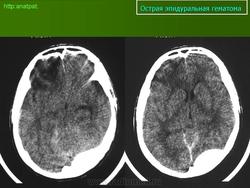

3. Эпидуральная гематома основания черепа в области перелома задней черепной ямки (указано стрелками)